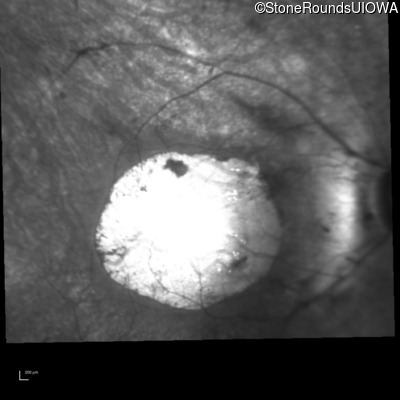

Infrared Fundus Photograph - Right - 20/125

Exemplar